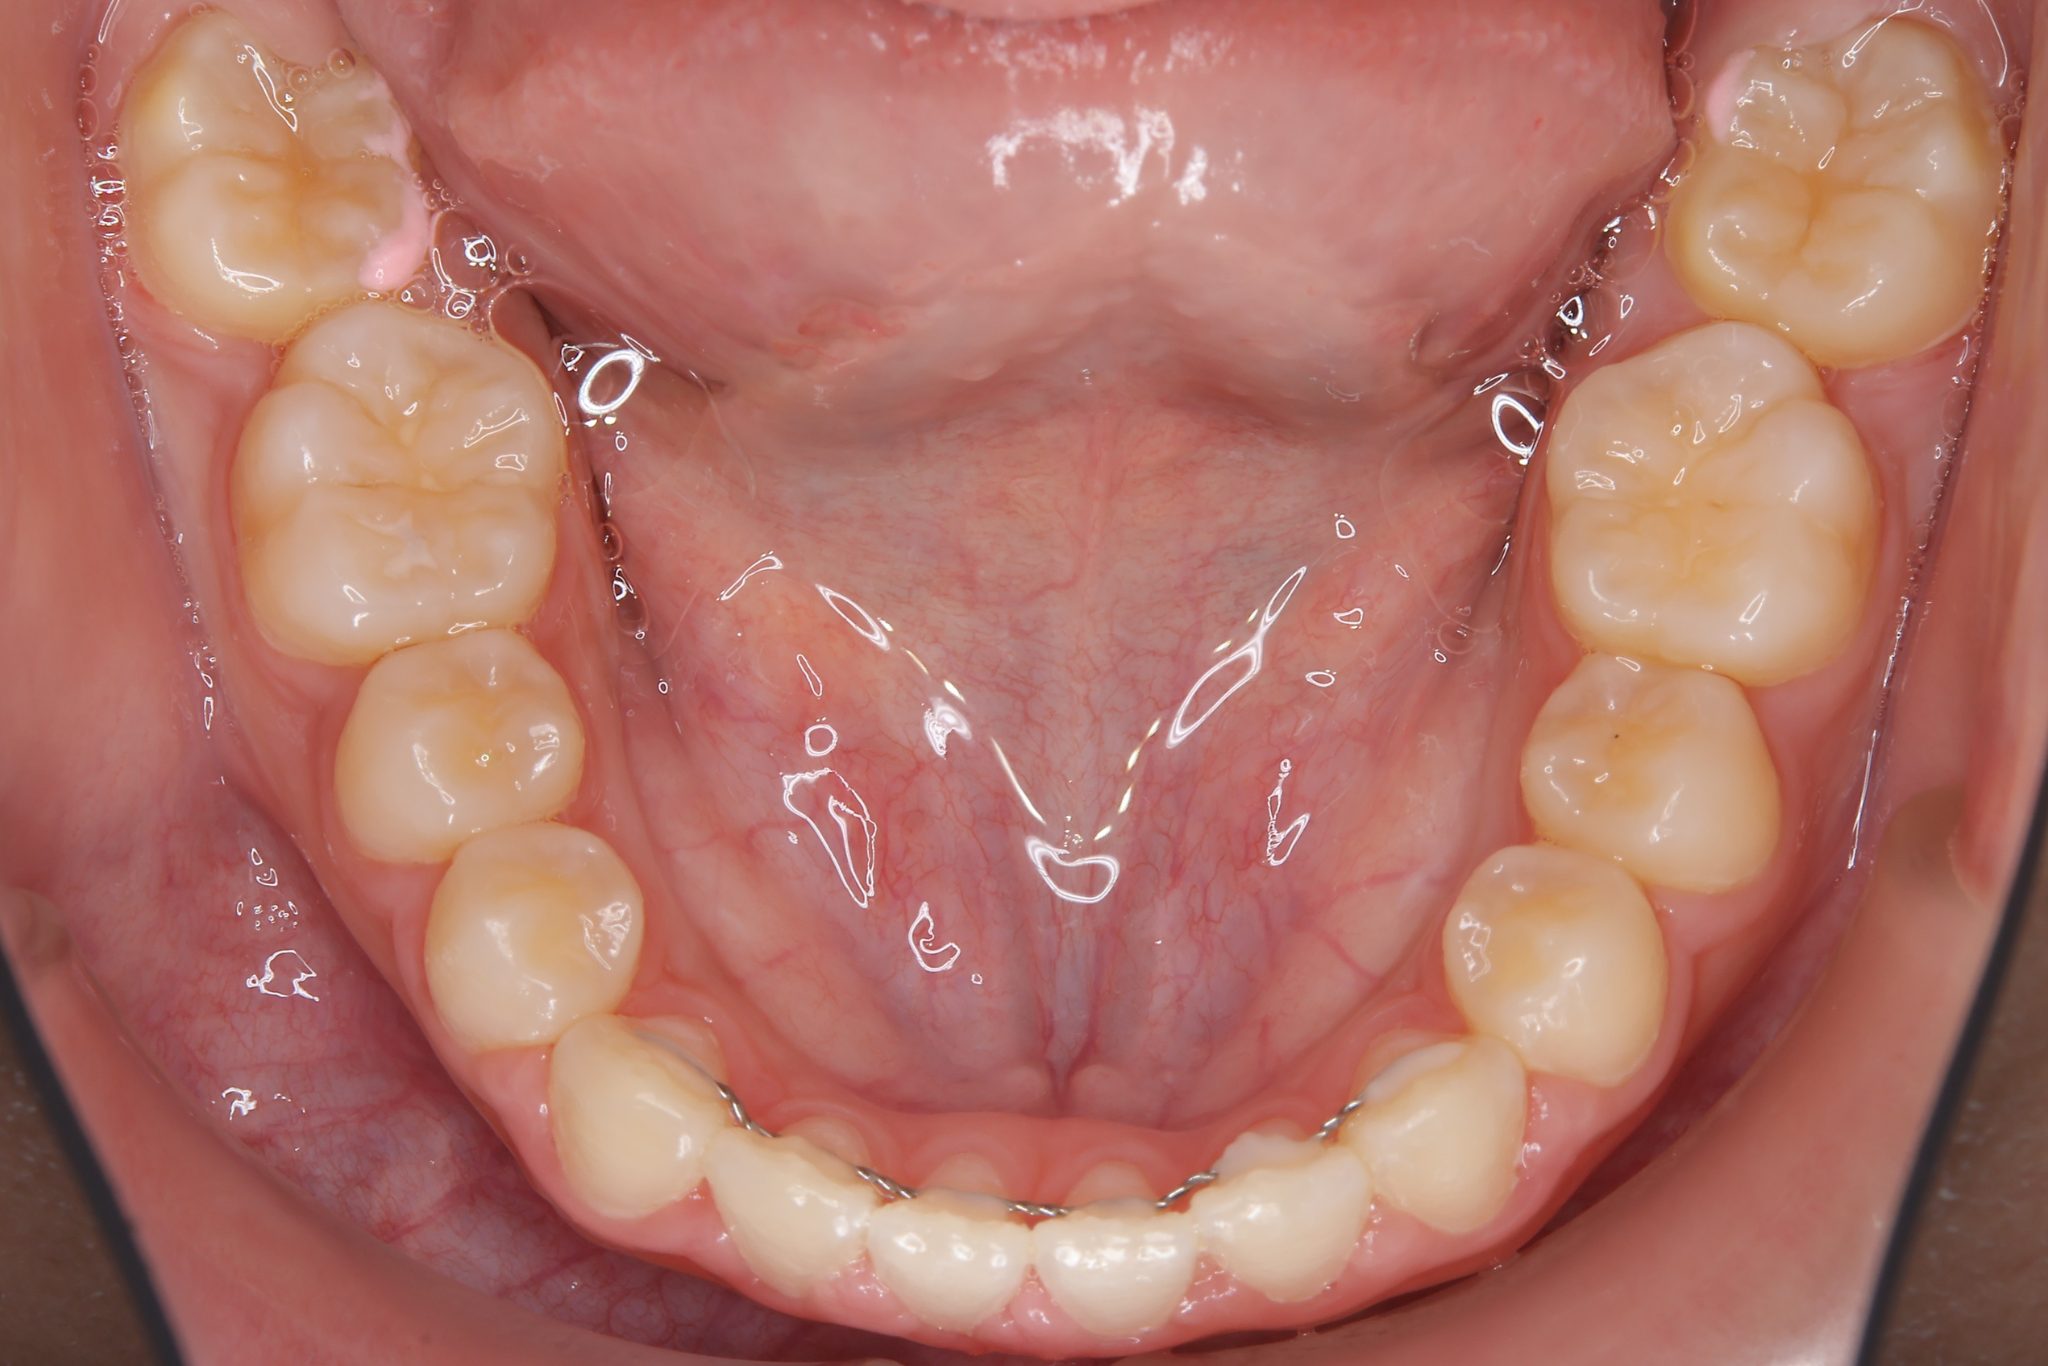

ビフォー

主訴 上前歯が出ている|よく口が開いている

施術内容 上顎急速拡大装置と下顎リンガルアーチを用いて上下顎骨を拡大した。

その後マルチブラケット装置を用いて

非抜歯で歯牙を配列し良好な咬合を獲得した。

鼻閉症状は改善した。

治癒期間 2年10か月間